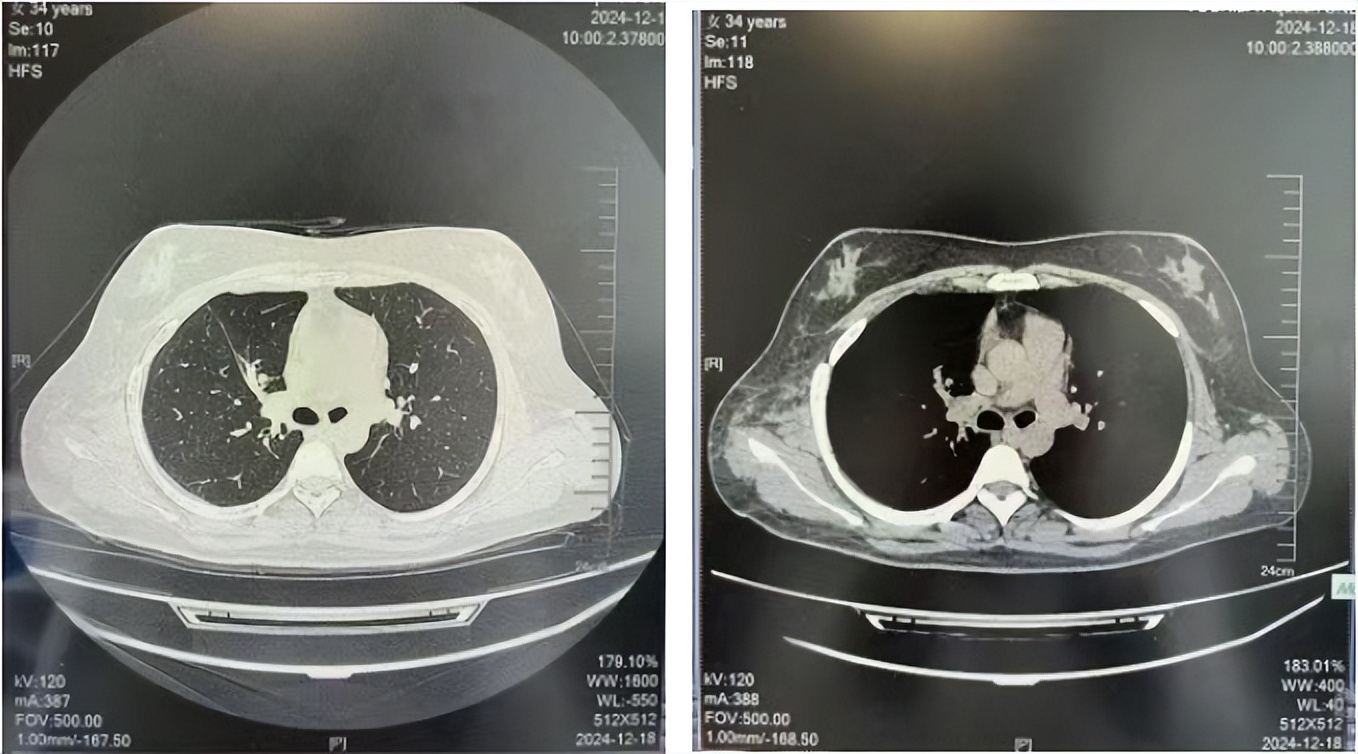

56岁,女性,无吸烟史饮酒史,既往体健。2023年02月患者体检发现肺占位性病变,胸部增强CT:右肺下叶后基底段结节;右侧锁骨上及纵隔内多发淋巴结肿大。PET-CT:右肺下叶周围型肺癌可能性大;1R、2L、3P、4R、4L及7组淋巴结转移可能性大。2023年02月就诊于本院胸外科行超声胃镜下纵隔肿物穿刺活检术,病理:结合免疫组化,符合肺腺癌。行NGS基因检测:EML4:exon20-ALK:exon20融合。PD-L1(克隆号22C3)TPS=55%。

临床诊断:右肺下叶恶性肿瘤cT1bN3M0,IIIB(第9版分期),纵隔淋巴结继发恶性肿瘤,锁骨上淋巴肿继发恶性肿瘤

治疗经过:2023年3月27日始行恩沙替尼靶向治疗至今,最佳疗效为PR,末次评效为维持PR。期间出现轻度肝功能异常(DILI 1级),对症处理后好转。截止目前PFS为26个月。

2023年2月20日基线检查

2024年6月复查PR(最佳疗效)

2024年12月复查维持PR

2025年3月复查维持PR